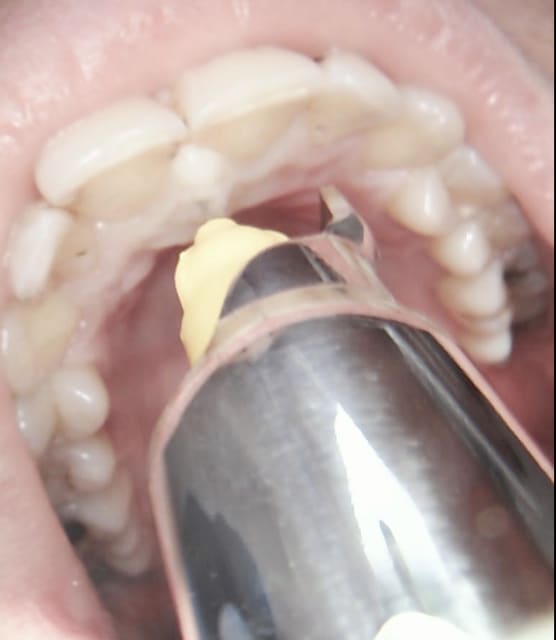

Trigone rétro molaire en général.

Aussitot dit aussitot fait. -))))

Signe de vincent mais pas la langue en vrac. C'est simple c'est tout droit au fond et en vestibulo distal de la dernière molaire tu sens une petite dépression au pouce l'os y est plus tendre. -)))))